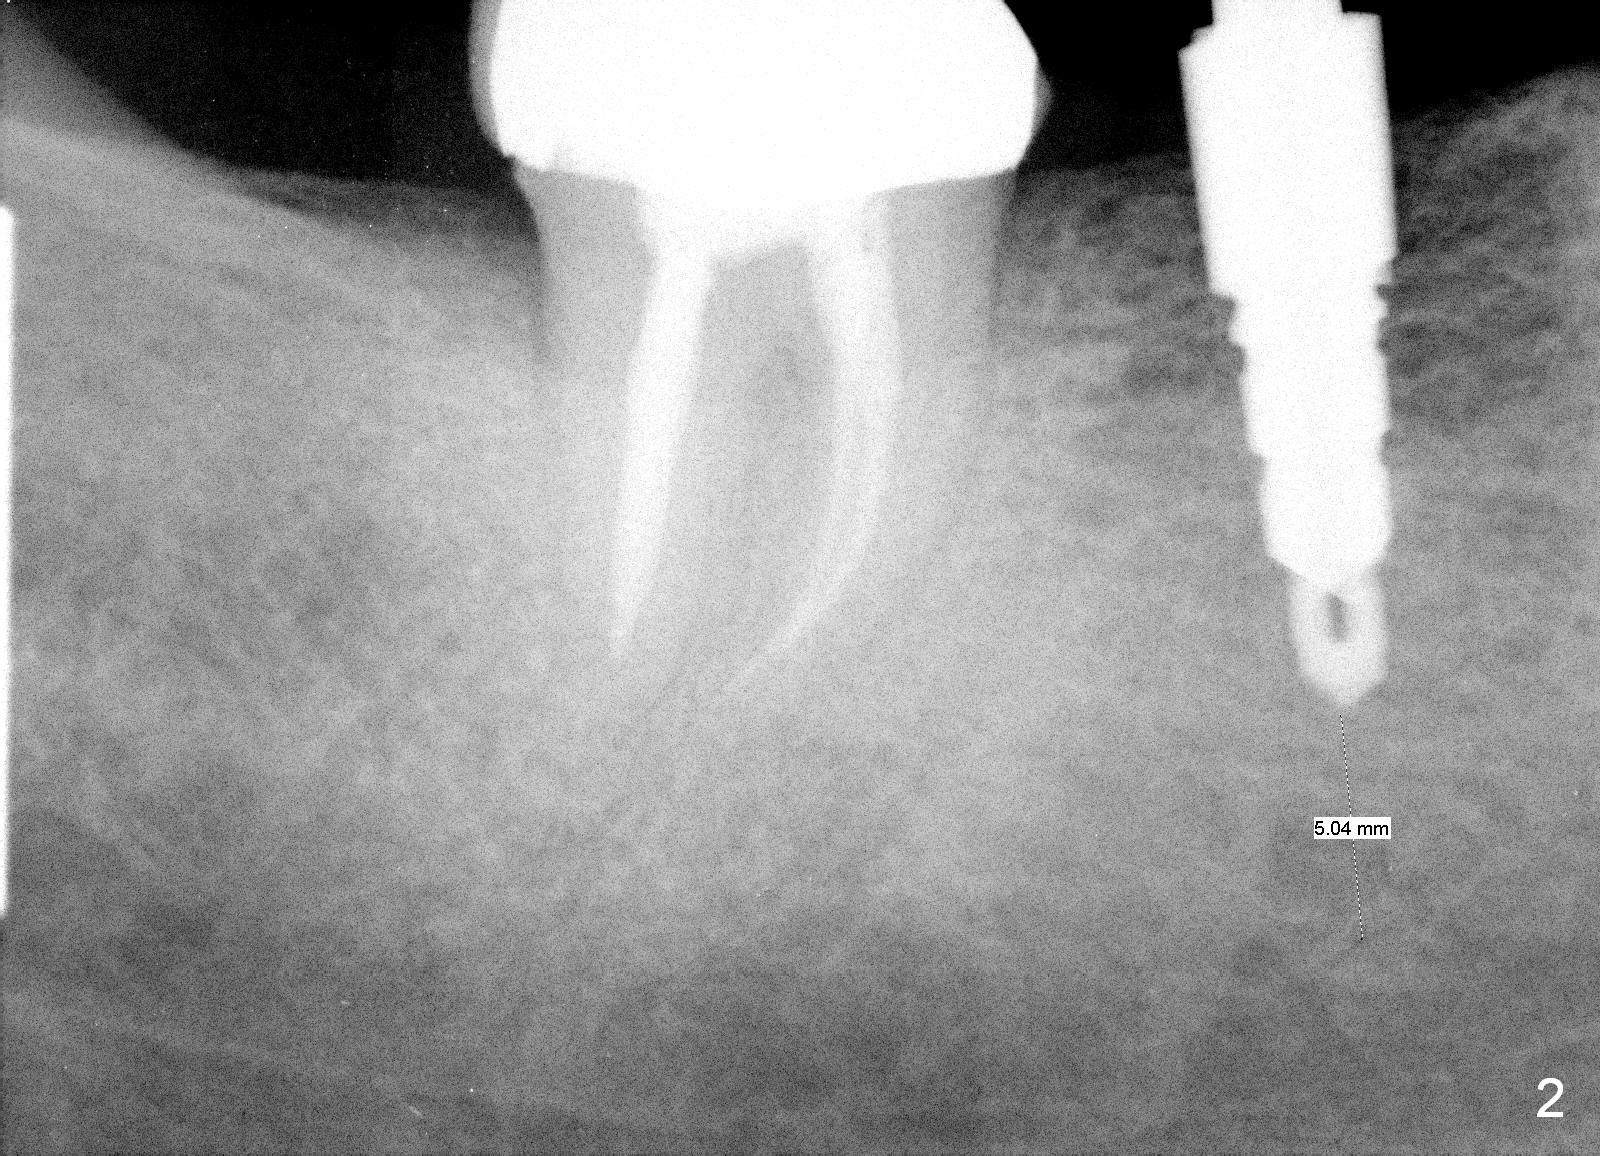

A 47-year-old man has history of bruxism, chipping porcelain from #29-31 FPD (Fig.1). Following sectioning the FPD, osteotomy is created (Fig.2: 5x14 mm drill) for placement of a 5x14 mm tissue-level implant (Fig.3,4). A 4x3 mm abutment (Fig.5 (lingual view) A) with 3 vertical slots (* for increased retention) is placed to retain periodontal dressing. The crown over the implant has dislodged 3 times over 28 months post cementation (Fig.6). It appears that the top of the abutment is too rounded. Clinical exam shows that the abutment height can be more, although the tooth #3 is supraerupted (Fig.7 (orthodontic intrusion is not indicated because of furca infection)).